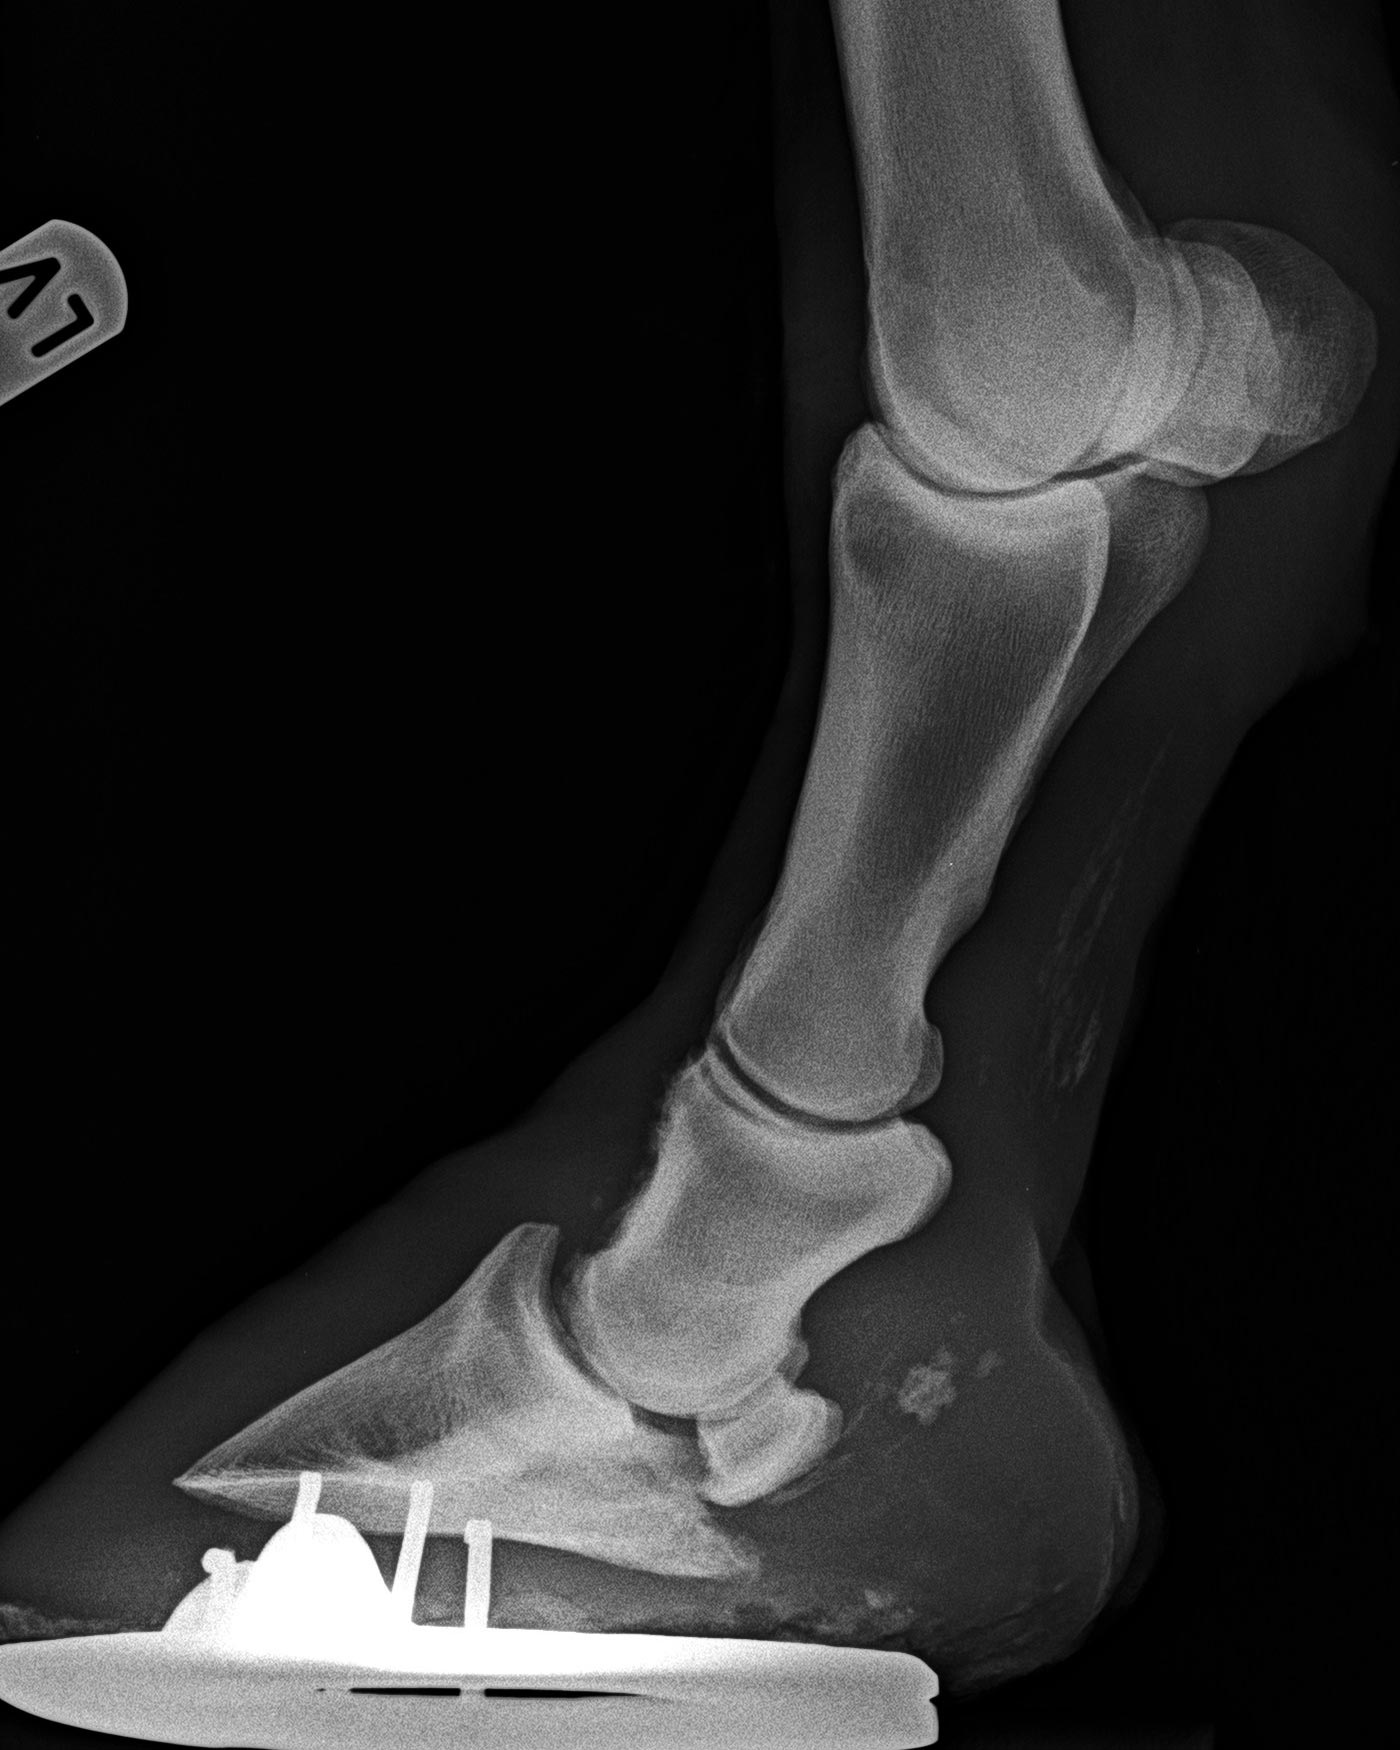

Zehe vorne links - 90°-Aufnahme

die gleiche Ansicht wie auf vorheriger Aufnahme 6 Monate später,

die Luxation im Hufgelenk hat erheblich zugenommen, die Prognose ist infaust